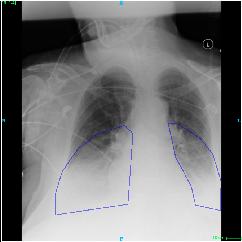

Fig.Β 5: Examples of class activation maps of positive cases. Left to right: image with annotation in blue, no L1 regularization, with L1 regularization, baseline.

Fig. 5 shows examples of class activation maps of positive cases for visual comparisons among the final models. These were produced using the Grad-CAM approach [14]. The images were annotated by an expert for the regions of opacity. Although all models correctly classified the cases as positives, the activation maps of the baseline model were barely correlated with the annotated regions, with more irrelevant hot spots outside the lungs. On the other hand, the activation maps of the models with feature selections were better correlated with the annotation. In other words, these smaller networks seems to be also more focused on the correct regions, which is a step towards explainability. The image in the third row shows that the VGG16 activation map has important components outside the lungs, focusing on English characters on the image. Whereas the reduced networks show more activation in marked areas of the lungs.